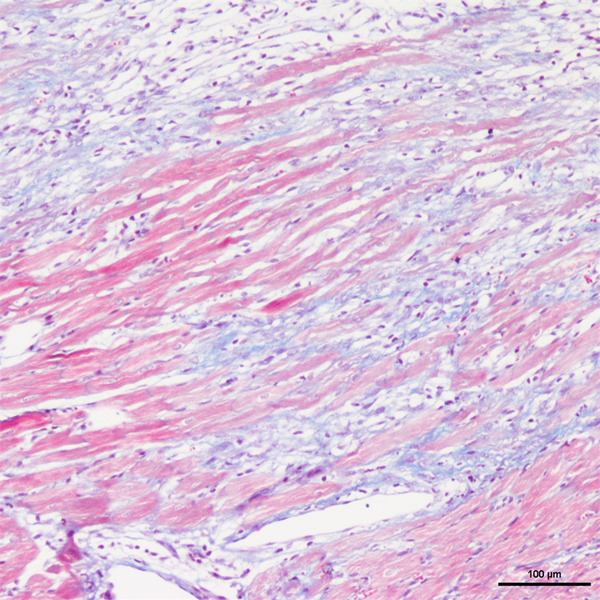

Masson染色

丽春红酸性品红-苯胺蓝染色,是用于检测动物组织中胶原纤维的一种染色方法之一,能够将胶原纤维染成蓝色,肌纤维、和红细胞呈红色,可用于鉴胶原纤维和肌纤维;并显示各种组织胶原纤维含量及纤维化程度。

Masson染色时胶原纤维呈蓝色(被苯胺蓝所染)或绿色(被亮绿所染),肌纤维呈红色(被酸性品红和丽春红所染),这与阴离子染料分子的大小和组织的渗透性有关。如已固定的组织用一系列阴离子水溶性染料先后或混合染色,则可发现红细胞被最小分子的阴离子染料着染,肌纤维与胞质被中等大小的阴离子染料着染,而胶原纤维则被大分子的阴离子染料着染。由此说明了红细胞对阴离子染料的渗透性最小,肌纤维与胞质次之,而胶原纤维具有最大的渗透性。根据组织不同的渗透性能,选择分子大小不同的阴离子染料进行染色,便可把不同组织成分显示出来。

实验结果展示: